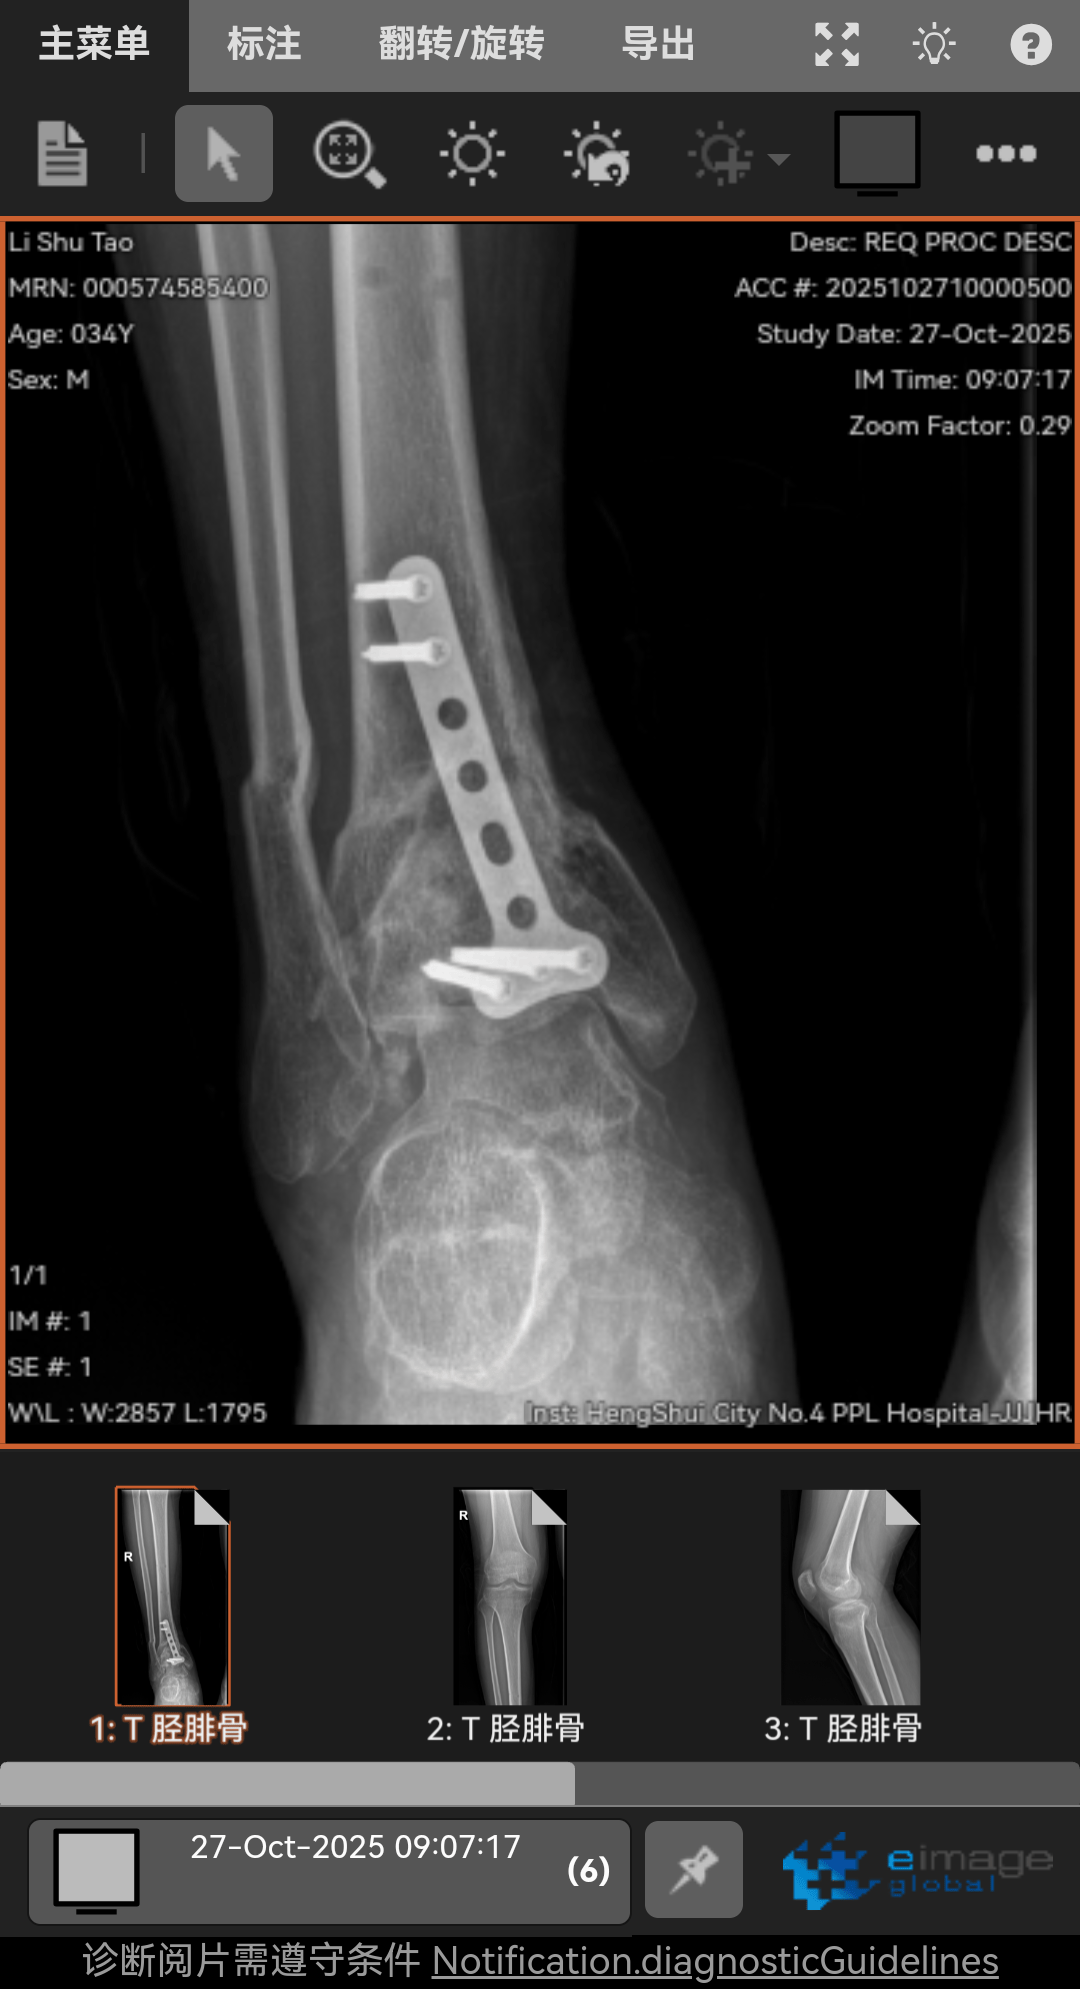

高坠骨折,6个月了,脚底板麻木,按压有刺痛,我是汗脚现在脚底板干燥,怎么办呢?走路腿特别沉重脚踝活动还不行,膝盖伸不直有点积液,怎么办呢!求求兄弟姐妹你们了。